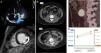

A su llegada, el paciente presentaba tendencia a la hipertensión (190/90mmHg) y taquicardia (130lpm), con elevación del segmento ST septal <1mm en el electrocardiograma. Presentaba cardiomegalia en la radiografía de tórax y elevación de troponina I, leucocitosis y neutrofilia en la analítica sanguínea. El ecocardiograma mostró hipocinesia difusa y dilatación del ventrículo izquierdo con insuficiencia mitral grave y fracción de eyección del ventrículo izquierdo del 15%. La sospecha inicial fue de miocarditis infecciosa, por el antecedente de una picadura de garrapata. En la resonancia magnética cardiaca se observó realce tardío sugestivo de necrosis y un trombo apical (fig. 1). Pese al inicio de la anticoagulación, presentó un ictus isquémico cardioembólico por el que se trasladó a nuestro centro para realización de trombectomía mecánica y completar el estudio cardiológico.

Algoritmo diagnóstico de la disfunción ventricular grave por feocromocitoma. A) Miocardiopatía dilatada de novo con insuficiencia mitral funcional grave. Además, en la resonancia magnética cardiaca se observa el realce tardío compatible con infarto. B) Crecimiento de la masa retroperitoneal. C) Tomografía por emisión de positrones. D) Niveles de las metanefrinas.

Se inició tratamiento con alfa bloqueo a altas dosis (fenoxibenzamina 90mg/día), expansión de volumen y posteriormente, tratamiento con bloqueadores beta a dosis bajas por tendencia a hipotensión. En situación clínica estable, tras 21 días de tratamiento, se realizó cirugía por vía laparoscópica. La evolución clínica y ecocardiográfica fue favorable: 30 días después, se encontraba en clase funcional I de la New York Heart Association, con mejoría de la fracción de eyección del ventrículo izquierdo (35%), de las presiones pulmonares, y la práctica desaparición de la insuficiencia mitral. Sesenta días más tarde, presentaba fracción de eyección del ventrículo izquierdo del 45% sin otras alteraciones. Finalmente, la anatomía patológica confirmó la sospecha, y presentó inmunohistoquímica compatible con un subtipo de bajo riesgo de síndrome de paraganglioma familiar (tipo 5, por mutación en la enzima Succinate Dehydrogenase Subunit A [SDHA]). Se solicitó estudio genético5 aún pendiente de resultados. Se confirma que se obtuvo el consentimiento informado del paciente.

Existen 2 grupos fundamentales de cardiopatías secundarias a feocromocitomas: la de estrés/tako-tsubo, en la que un desencadenante genera una importante crisis adrenal, y la catecolaminérgica (CC)4, tras una exposición repetida y crónica. Ambas entidades se presentan de forma similar en fase aguda: disfunción ventricular de novo acompañada de síntomas sugestivos de feocromocitoma, si bien su fisiopatología y recuperación difiere. La cardiopatía tako-tsubo tiende a presentar un curso agudo, con mayor recuperación (95% casos frente al 75%) en menos tiempo (mediana de 14 días frente a 30) que la catecolaminérgica4. En nuestro caso, la cardiopatía apuntaba a que era catecolaminérgica: el paciente presentaba una masa desde hacía 6 años, con un importante remodelado ventricular desde el principio, sin segmentarismos y los cambios eléctricos podían explicarse por un infarto embólico. Además, la recuperación fue lenta pero progresiva (tabla 1).